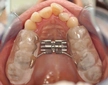

Dogo Çenesinin Gücü Ne Kadar Ton Basabiliyor?Dogo Argentino, güçlü yapısıyla dikkat çeken bir köpek ırkıdır. Bu ırk, av köpeği olarak yetiştirilmiş olup, kaslı yapısı ve güçlü çenesi ile bilinir. Dogo Argentino'nun çene gücü, hem avcılık yetenekleri hem de koruma işlevleri açısından oldukça önemlidir. Bu makalede, Dogo'nun çene gücünü detaylı bir şekilde inceleyeceğiz. Dogo Argentino'nun Çene AnatomisiDogo Argentino, güçlü bir çene yapısına sahip olmasıyla birlikte, bu güçlü yapı birkaç anatomik özellikten kaynaklanmaktadır:

Çene Gücü ve Basınç ÖlçümüBir köpeğin çene gücünü ölçmek için genellikle "bite force" (ısırma gücü) terimi kullanılır. Dogo Argentino'nun çene gücü, 450 psi (pound per square inch) civarında ölçülmüştür. Bu, Dogo'nun çenesinin yaklaşık 20-30 ton basma kapasitesine sahip olduğu anlamına gelir. Bu güç, Dogo'nun avını yakalama ve tutma yeteneğini büyük ölçüde artırır. Çene Gücünün ÖnemiDogo Argentino'nun çene gücü, birkaç açıdan önem taşımaktadır: